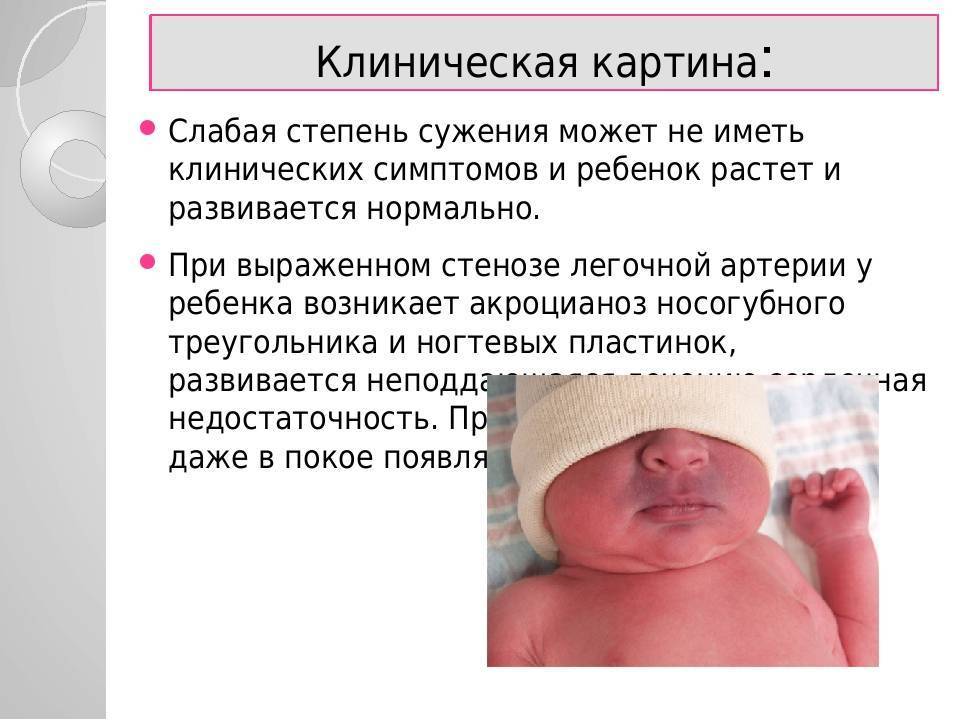

Врожденные пороки сердца делят на 2 группы: белые и синие.

При белых, или бледных, порока сердца, не происходит смешивание артериальной и венозной крови. К белым порокам относят: дефект межпредсердной перегородки, дефект межжелудочковой перегородки, АВ-коммуникацию, сужение (стеноз) легочной артерии, аортальный стеноз, коарктацию аорты, пр.

При синих пороках сердца происходит смешивание артериальной и венозной крови. Примеры синих врожденных пороков сердца: комплекс Эйзенменгера, полная транспозиция магистральных сосудов, тетрада Фалло, аномалия Эбштейна, пр.

Виды врожденных патологий сердца

- Дефекты клапанов сердца. Дефекты клапанов сердца могут стать причиной сужения (или стеноза) клапанов, а также их полного закрытия, что препятствует нормальному кровотоку. Другие проблемы могут быть связаны с тем, что клапаны не закрываются так, как это необходимо, тем самым не позволяя крови течь в обратном направлении.

- Дефекты перегородок между предсердиями и желудочками. Отверстия между камерами сердца могут привести к смешиванию обогащенной и не обогащенной кислородом крови между правой и левой сторонами сердца, чего в норме быть не должно.